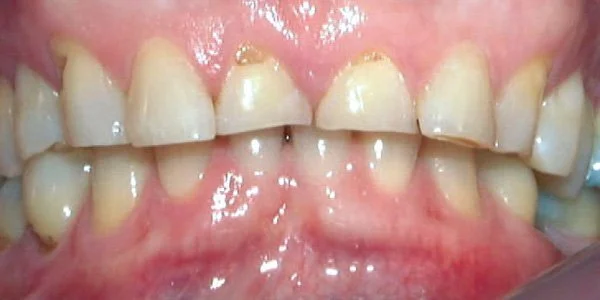

Periodontal Problems

A bad bite can contribute to gum recession & loss of support for teeth.